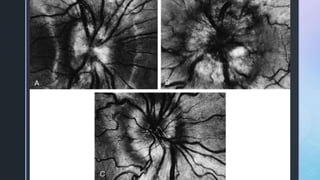

• #27Ā A, Moderate papilledema-The nerve fiber layer has mild distortion of light reflexes and a muddy appearance obscuring small vessels traversing the disc margin. B, Marked papilledema-The reflexes from the peripapillary retinal nerve fiber layer are completely distorted and blurred. C, Pseudopapilledema-Although the disc is moderately elevated, the surface vessels appear normal and the nerve fiber layer reflexes are sharply defined.